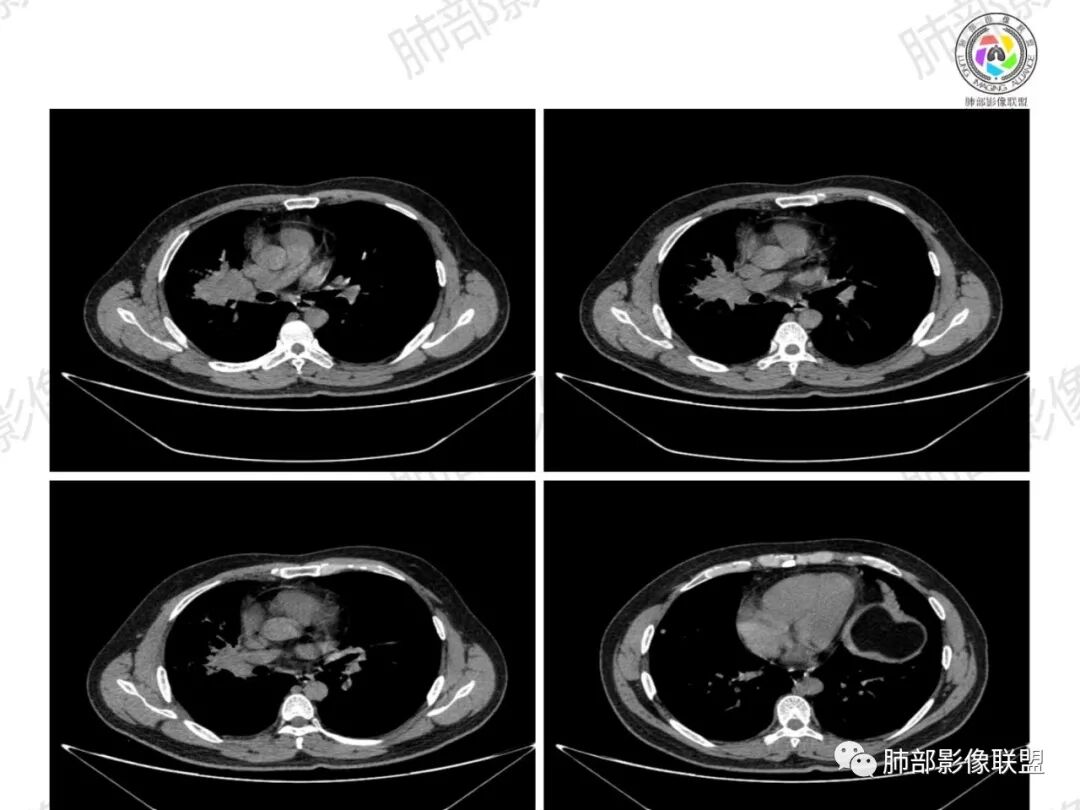

了:中年男性,右肺门肿块影,浅分叶,周围晕征,边缘清楚,小叶间隔增厚,树芽征,支气管截断,不均匀强化,内可见低密度坏死,纵隔淋巴结肿大,综合考虑肺部肿瘤并阻塞性肺炎

一切∮随缘:右肺门肿块影形态不规则,边缘毛糙,右肺上叶支气管堵塞,病变跨叶生长,远端血管束增粗,周围散在多发结节,部分位于胸膜下,平扫密度尚均匀,增强后不均匀强化,呈中度强化,坏死区无强化,纵隔淋巴结肿大。临床无感染症状,考虑恶性,鳞癌,腺癌,鉴别慢性脓肿。

周太狼:中年男性,吸烟史,陈旧结核史,呼吸道症状未提及,抗感染治疗无效。影像见右上肺门区软组织肿块影,浅分叶、毛刺,支气管似有截断,其内密度不均匀,不均匀强化,内可见低密度坏死区,病壮周围见斑片、结节影。纵隔内淋巴结稍肿大,首先考虑恶性,肺部肿瘤并阻塞性肺炎,肺鳞癌可能,鉴别结核。

弹指之间:中年男性,结核史、吸烟;右肺门肿块,特点:右肺上叶尖、前段支气管狭窄、部分阻塞(肿块大、支气管狭窄闭塞相对轻),肿块内血管部分残留(生长速度快,浸润>破坏),周围见渗出、炎症,部分实变;内见坏死、位于边缘区域;纵隔淋巴结肿大;考虑恶性,1.非支气管粘膜起源首先考虑,淋巴瘤?(但坏死相对多了);2.鳞癌(支气管阻塞轻);3.小细胞待排。

浅分叶,内部坏死部分边界不清,实性部分明显强化

环形强化

纵隔淋巴结肿大并不明显,就这一个肿大较明显,但仍呈椭圆形,中心少许坏死。